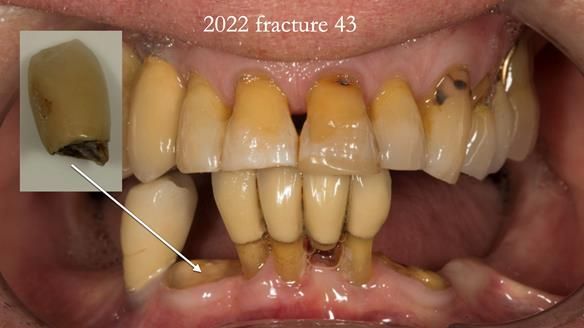

In 2022, tooth 43 fractured.

An artificial tooth was added to the RPD

by welding a cobalt–chrome tag to the bar

and adding the tooth.

The denture continued to function extremely well.